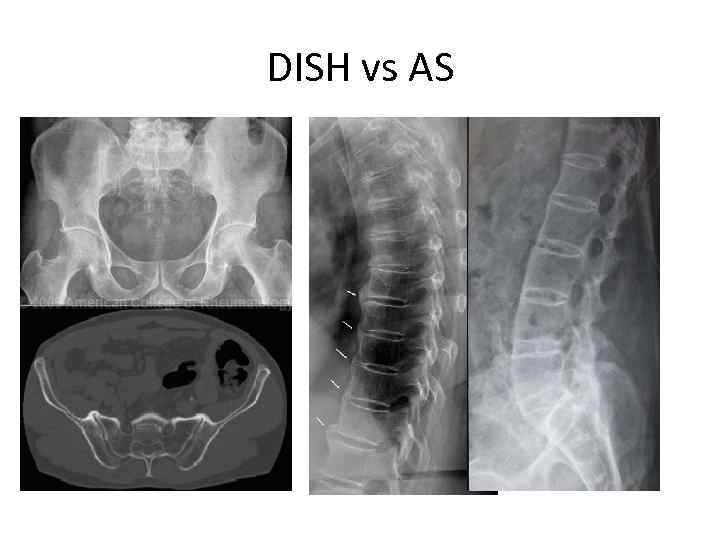

DISH vs AS